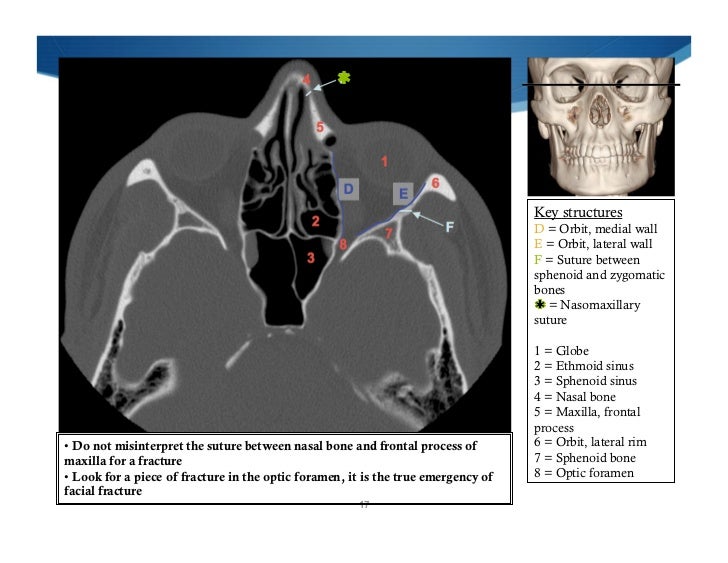

Imaging Of Facial Trauma Part 1

sinus

Imaging of facial trauma part 1. Neurosurgicalatlas correlation. Skull bones labeled eye anterior nasal septum upper sockets form shows human orbits cavity forehead jaws lower